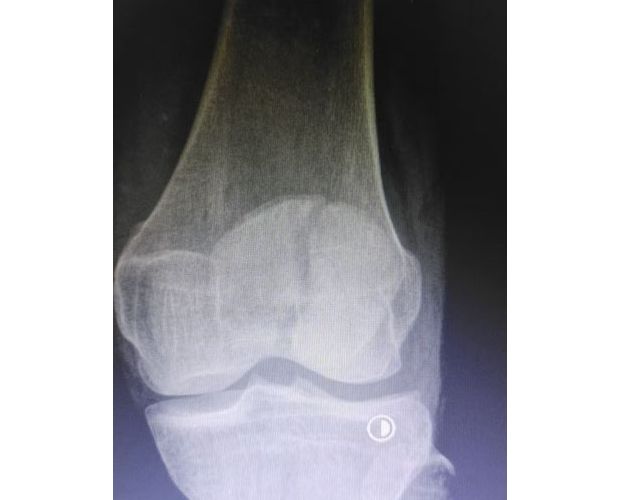

隨州新聞網訊 (通訊員王靜、陳勇)為深入推進緊密型醫共體建設,切實讓轄區群眾在家門口就能享受到優質、便捷的醫療服務,以醫療便民舉措為優化營商環境注入健康活力,3月31日中午,何店鎮中心衛生院(隨州市曾都區人民醫院何店分院)依托醫共體資源優勢,特邀曾都區人民醫院脊柱創傷外科主任徐三軍到該院,成功為一名47歲髕骨骨折患者實施髕骨骨折切開復位內固定手術,用專業診療守護群眾健康,用務實行動踐行便民宗旨。

精湛施術 安全有序,守護患者健康

手術現場,徐三軍主任憑借多年積累的臨床經驗和嫻熟的手術技巧,精準完成骨折復位、鋼板內固定、傷口縫合等一系列關鍵操作,動作規范流暢、精準高效,最大限度減少手術創傷。該院外科醫護團隊全程密切配合、協同發力,嚴格按照手術規范操作,全程嚴密監測患者心率、血壓等生命體征,及時應對術中各類突發情況,全力保障手術安全。此次手術全程順利,術中出血量少,患者生命體征始終平穩,術后患者順利安返病房,為后續康復治療奠定了堅實基礎。